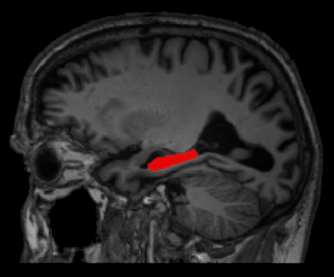

Methods for the analysis and characterization of brain morphology from MRI images

Brain magnetic resonance imaging (MRI) is one of the most commonly used methods for investigating brain morphology, since it allows to produce detailed 3D images of its soft-tissue structures. In this project, we are working on the development of methods for the analysis and characterisation of brain morphology from brain MRI images.